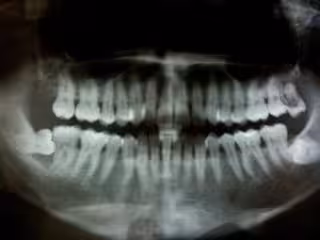

Periodontitis

La periodontitis daña los tejidos que soportan y rodean los dientes. En estados avanzados, "cuando existe una destrucción del periodonto, la enfermedad puede ser muy dolorosa, irreversible y puede suponer la pérdida de una o más dientes", comenta Escorial. Además, esta patología está relacionada con otras afecciones como la diabetes, el deterioro cognitivo o las enfermedades cardiovasculares.

Si, tras la evaluación de los resultados de distintas pruebas, el tratamiento no muestra resultados o se trata de una periodontitis muy agresiva, la experta detalla que los dentistas pueden sugerir la realización de pruebas específicas, como el análisis de ADN y el estudio microbiológico.

El análisis de ADN, según explica, puede determinar si el paciente es portador o no de alguna de las bacterias más implicadas en la prevalencia de las enfermedades periodontales, y recomendar algún cuidado específico para retrasar y prevenir el desarrollo de patologías. Por otra parte, el estudio microbiológico permite conocer qué tipo de bacterias se localizan en la cavidad bucodental. La prueba es "indolora" y consiste en el análisis y cultivo de una muestra de fluido crevicular para conocer los factores que influyen en el desarrollo de la enfermedad: evolución, zonas más afectadas y antibióticos más efectivos contra la bacteria.

"Este tipo de estudio se realiza cuando el diagnóstico clínico-radiológico apunta a que el tipo de periodontitis es agresiva. El tratamiento mecánico va acompañado de una antibioterapia selectiva (que establecemos mediante este estudio microbiológico) contra las bacterias responsables de esta evolución mucho más severa. Al mismo tiempo, podemos establecer una pauta de seguimiento individualizada y mucho más rigurosa y conocer si la enfermedad se encuentra en una fase de estabilización", expone Escorial.